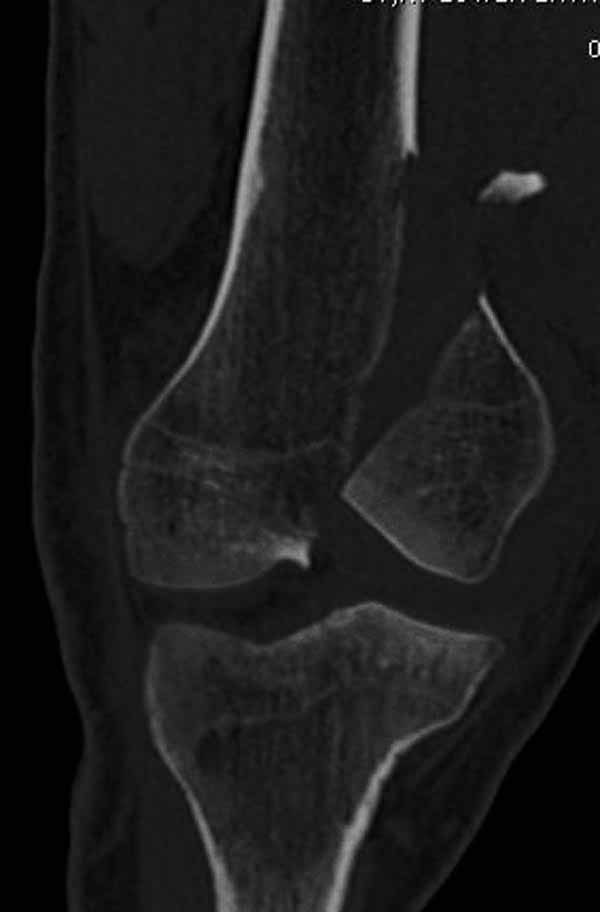

Остеосинтез, вестимо. КТ предварительно можно сделать, чтобы поточнее увидеть повреждения в межмыщелковой области. Перелом ближе к 33C1.

Представленный снимок не дает полную информацию. Там вроде простой перелом, но на самом деле, кроме смещенного (латерального, возможно медиального?) мыщелка на второй проекции имеется медиальный короткий дистальный фрагмент в флексии. Надо было сделать прямой снимок с захватом малоберцовой, который ориентировал бы стороны. Без КТ обычный снимок в дистракции поможет разобраться в топографии фрагментов.

Во время фиксации надо соблюдать осторожность, особенно с коротким фрагментом на другой стороне. Обычно на прямой проекции трудно заметить флексионную деформацию мыщелка и упускается адекватная фиксация. Без пластины винты не смогут удержать, и мыщелок на второй стороне может сместиться. Для фиксации надо развернуть мыщелок и удержать винтами. Качество межмыщелковой репозиции надо проконтролировать артротомией. Из всех доступов только передне-латеральный доступ (Swashbuckler) даст обзор для ревизии качества фиксации, который в будущем может быть использован для артропластики.

Кстати, из вашего снимка, если отмечены вашим рентгенологом правильно, тогда получается снимок левого колена, и, соответственно, длинный переходящий в диафиз мыщелковый фрагмент находится медиально. Если так, тогда меняется сценарий фиксации!!!

И не обратите, коллега, пока не сделаете четкие анфасные снимки (лучше с дистракцией) где будет четко визуализироваться малоберцовая кость. Думается, что и КТ здесь будет уместно, дабы не пропустить возможное флексионное повреждение (перелом Hoffa).

А теперь по поводу лечения перелома. Среди всех чрез/меж-мыщелковых переломов в 38% сопровождются переломом в корональной плоскости, т.е перелом Hoffa. Nork et al, J Orthop Trauma, 87:564, 2005.